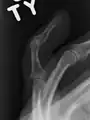

- La radiografía que muestra fractura en la inserción del tendón extensor

- Un dedo en martillo sin una fractura asociada